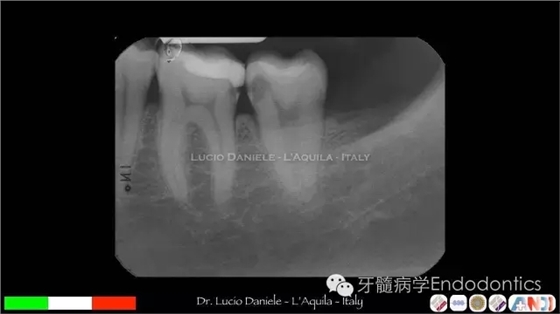

圖24.術后X線片